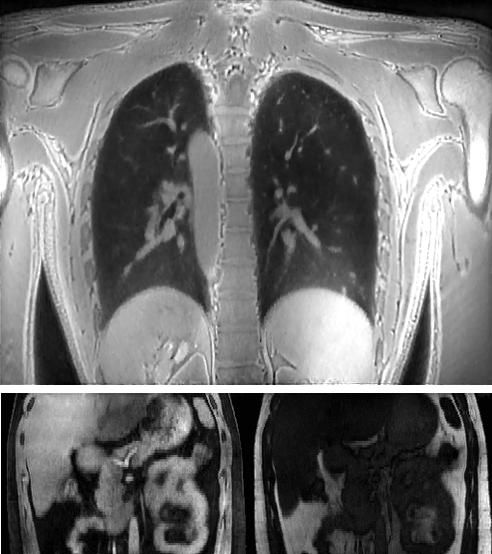

Medical imaging is now used extensively for accurate diagnosis, real-time intervention, and precision medicine. Our work has been focused on fast, high-resolution imaging augmented with functional and metabolic mapping. For example, dynamic 4D MRI under free breathing has been developed using PNCRNNs, with the reconstruction time as fast as 50 bin per second, offering substantial improvement of the image quality for dynamic golden-angle radial imaging of the abdomen. Novel imaging techniques have been developed for high-resolution whole-brain neurometabolic mapping, shedding light on in vivo molecular biomarkers for various brain diseases including stroke, brain tumor, and neurodegenerative disorders. A model-based deep learning architecture, referred to as MoDL-QSM, was developed with improved accuracy for quantifying tissue susceptibility for precise electrode implantation for deep-brain stimulation. To meet the demands for automated identification and localization of the vertebrae, pancreas, colon, lung nodules and other organs in low-dose CT, algorithms integrating local image details and global image patterns have been proposed. To extend the clinical use of nonlinear regression in medical imaging and image analysis, a deep negative correlation learning framework has been proposed to yield a deep regression of ensemble where each base model is both accurate and generalisable.

Dynamic 4D MRI of the abdomen

1. Zhang Y, She H, and Du YP. Dynamic MRI of the

abdomen using parallel non-cartesian convolutional recurrent neural networks.

Magnetic Resonance in Medicine, 2021, 86:964-973.